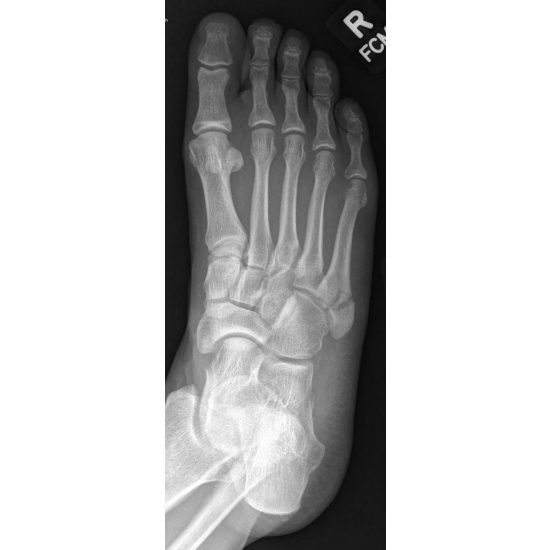

She continued with protected weight bearing in a walking boot and was later placed in a non-weight bearing cast for 4 weeks because of increasing diastasis of her fracture pieces. Case Photo #3 Case Photo #4